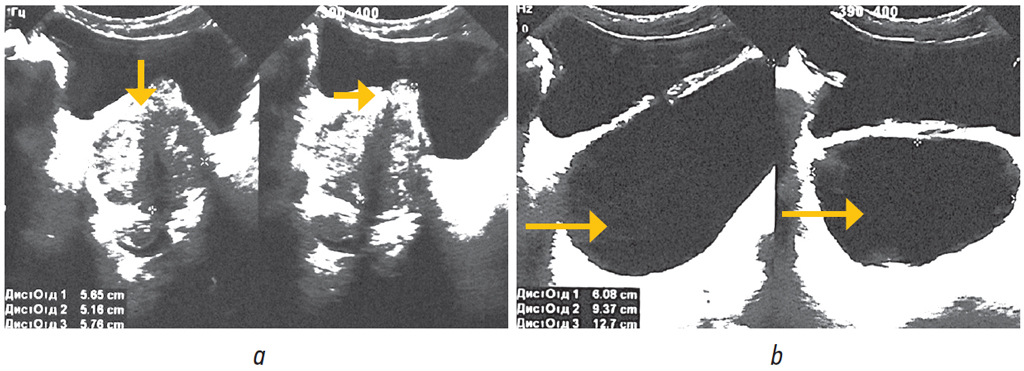

Пациент дообследован (рис. 3, 4). Лабораторные исследования выполнены в стандартном предоперационном объеме. Уровень простатического специфического антигена составил 1,27 нг/мл. При бактериологическом исследовании мочи роста микрофлоры не обнаружено. По данным опросника IPSS — 26 баллов, что соответствует тяжелой симптоматике, качество жизни (QoL) оценено в 4 балла. По данным ультразвукового исследования (рис. 3) объем предстательной железы составил 88 см3, интравезикальная протрузия простаты — Grade III (31 мм); объем мочевого пузыря 300 мл, объем остаточной мочи 132 мл, ДМП объемом 400 мл, опорожняющийся неудовлетворительно (300 мл).

Рис. 3. Ультрасонограмма пациента О., 68 лет: a — гиперплазия предстательной железы, стрелками указана ее «средняя доля»; b — дивертикул мочевого пузыря, указан стрелками / Fig. 3. Ultrasonogram of patient O., 68 years old: a — prostatic hyperplasia, arrows indicate the “middle lobe” of the prostate; b — bladder diverticulum, indicated by arrows

Рис. 4. Результаты обследования пациента О., 68 лет: а — экскреторная урография, выделительная функция почек нормальная; b — нисходящая цистография, определяется дивертикул, превосходящий по объему мочевой пузырь (указан стрелкой) / Fig. 4. The results of the examination of the patient O., 68 years old: a — intravenous urography, the excretory function of the kidneys is normal; b — descending cystography, the diverticulum is determined, exceeding the volume of the bladder (indicated by an arrow)